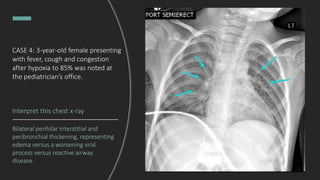

CASE 4: 3-year-old female

presenting with fever, cough and

congestion after hypoxia to 85%

noted at the pediatrician’s office.

Interpret this chest x-ray

Bilateral perihilar interstitial and

peribronchial thickening, representing

edema versus a worsening viral

process versus reactive airway

disease.